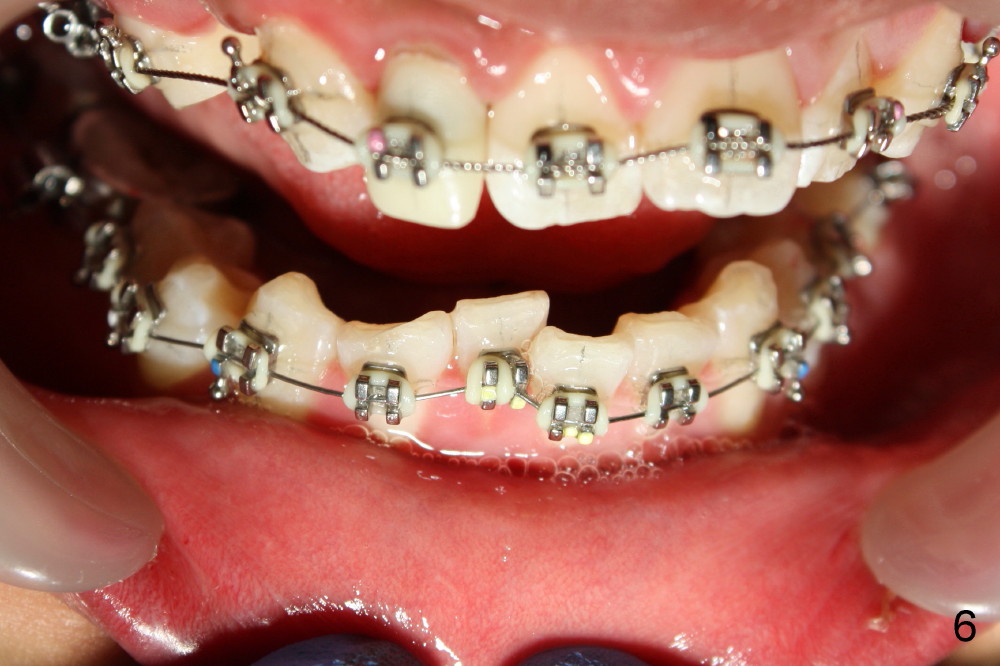

Fig.13-15 shows the upper incisors totally 4.5 month of retraction. The upper left canine (Fig.15: #11) seems to be distalized too much, as compared to the dashed line. Therefore whole arch power chain is placed with an intention to bring the canine mesially (arrowhead) while continue distalizing the incisors (including #10 (arrowhead).

One month of power chains appears to close the space between the lateral and canine (data not shown). Braided wires are placed; posterior interdigitation is under way.